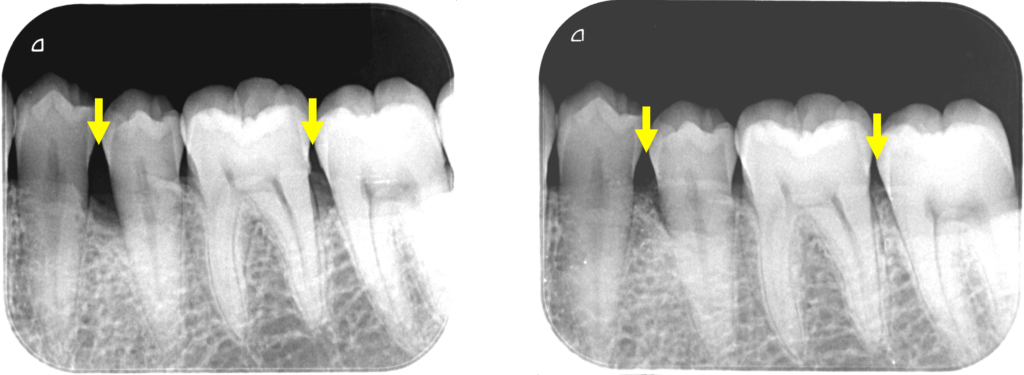

術前と術後1年半の比較です。

骨様組織で骨(歯槽骨)が溶けていた部分が満たされていることが確認できます。

歯肉退縮も最小限で良好な歯周組織を維持しています。